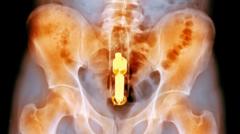

En este extremo del cuerpo, también se han encontrado cosas dentro del ano y el recto. Entre 66% y 85% de los que llegan a urgencias con esa queja son hombres.

Uno de los mayores problemas con objetos extraños en el ano o el recto es que se pueden atascar, obstaculizando el movimiento natural de la deposición intestinal. Con el tiempo, esto puede causar un ensanchamiento significativo del tracto con el riesgo de una perforación o ruptura del intestino.

Hay muchas razones por las cuales las personas se meten objetos extraños en el ano, desde las más comunes razones eróticas hasta las menos comunes para tratar el estreñimiento.

Aunque que las razones son diversas, la variedad de objetos encontrados por esos lares es mucho mayor. Incluyen manzanas, berenjenas, cepillos, bolígrafos, zanahorias, latas de pesticidas, latas de desodorante (con las que se corre el riesgo de incendio durante la cirugía para retirarlas), vasos, botellas de refresco, bolas de béisbol y probablemente el más doloroso, un coco entero.

El problema con los objetos extraños en el recto es que los esfínteres que mantienen tus heces adentro, hacen lo mismo que los objetos que son introducidos más allá de estos.

Muchos pueden estirar la pared muscular del recto hasta el punto en que no puede generar suficiente fuerza para expulsar el objeto, lo que significa que los cirujanos usualmente tiene que abrir al paciente para retirarlos.